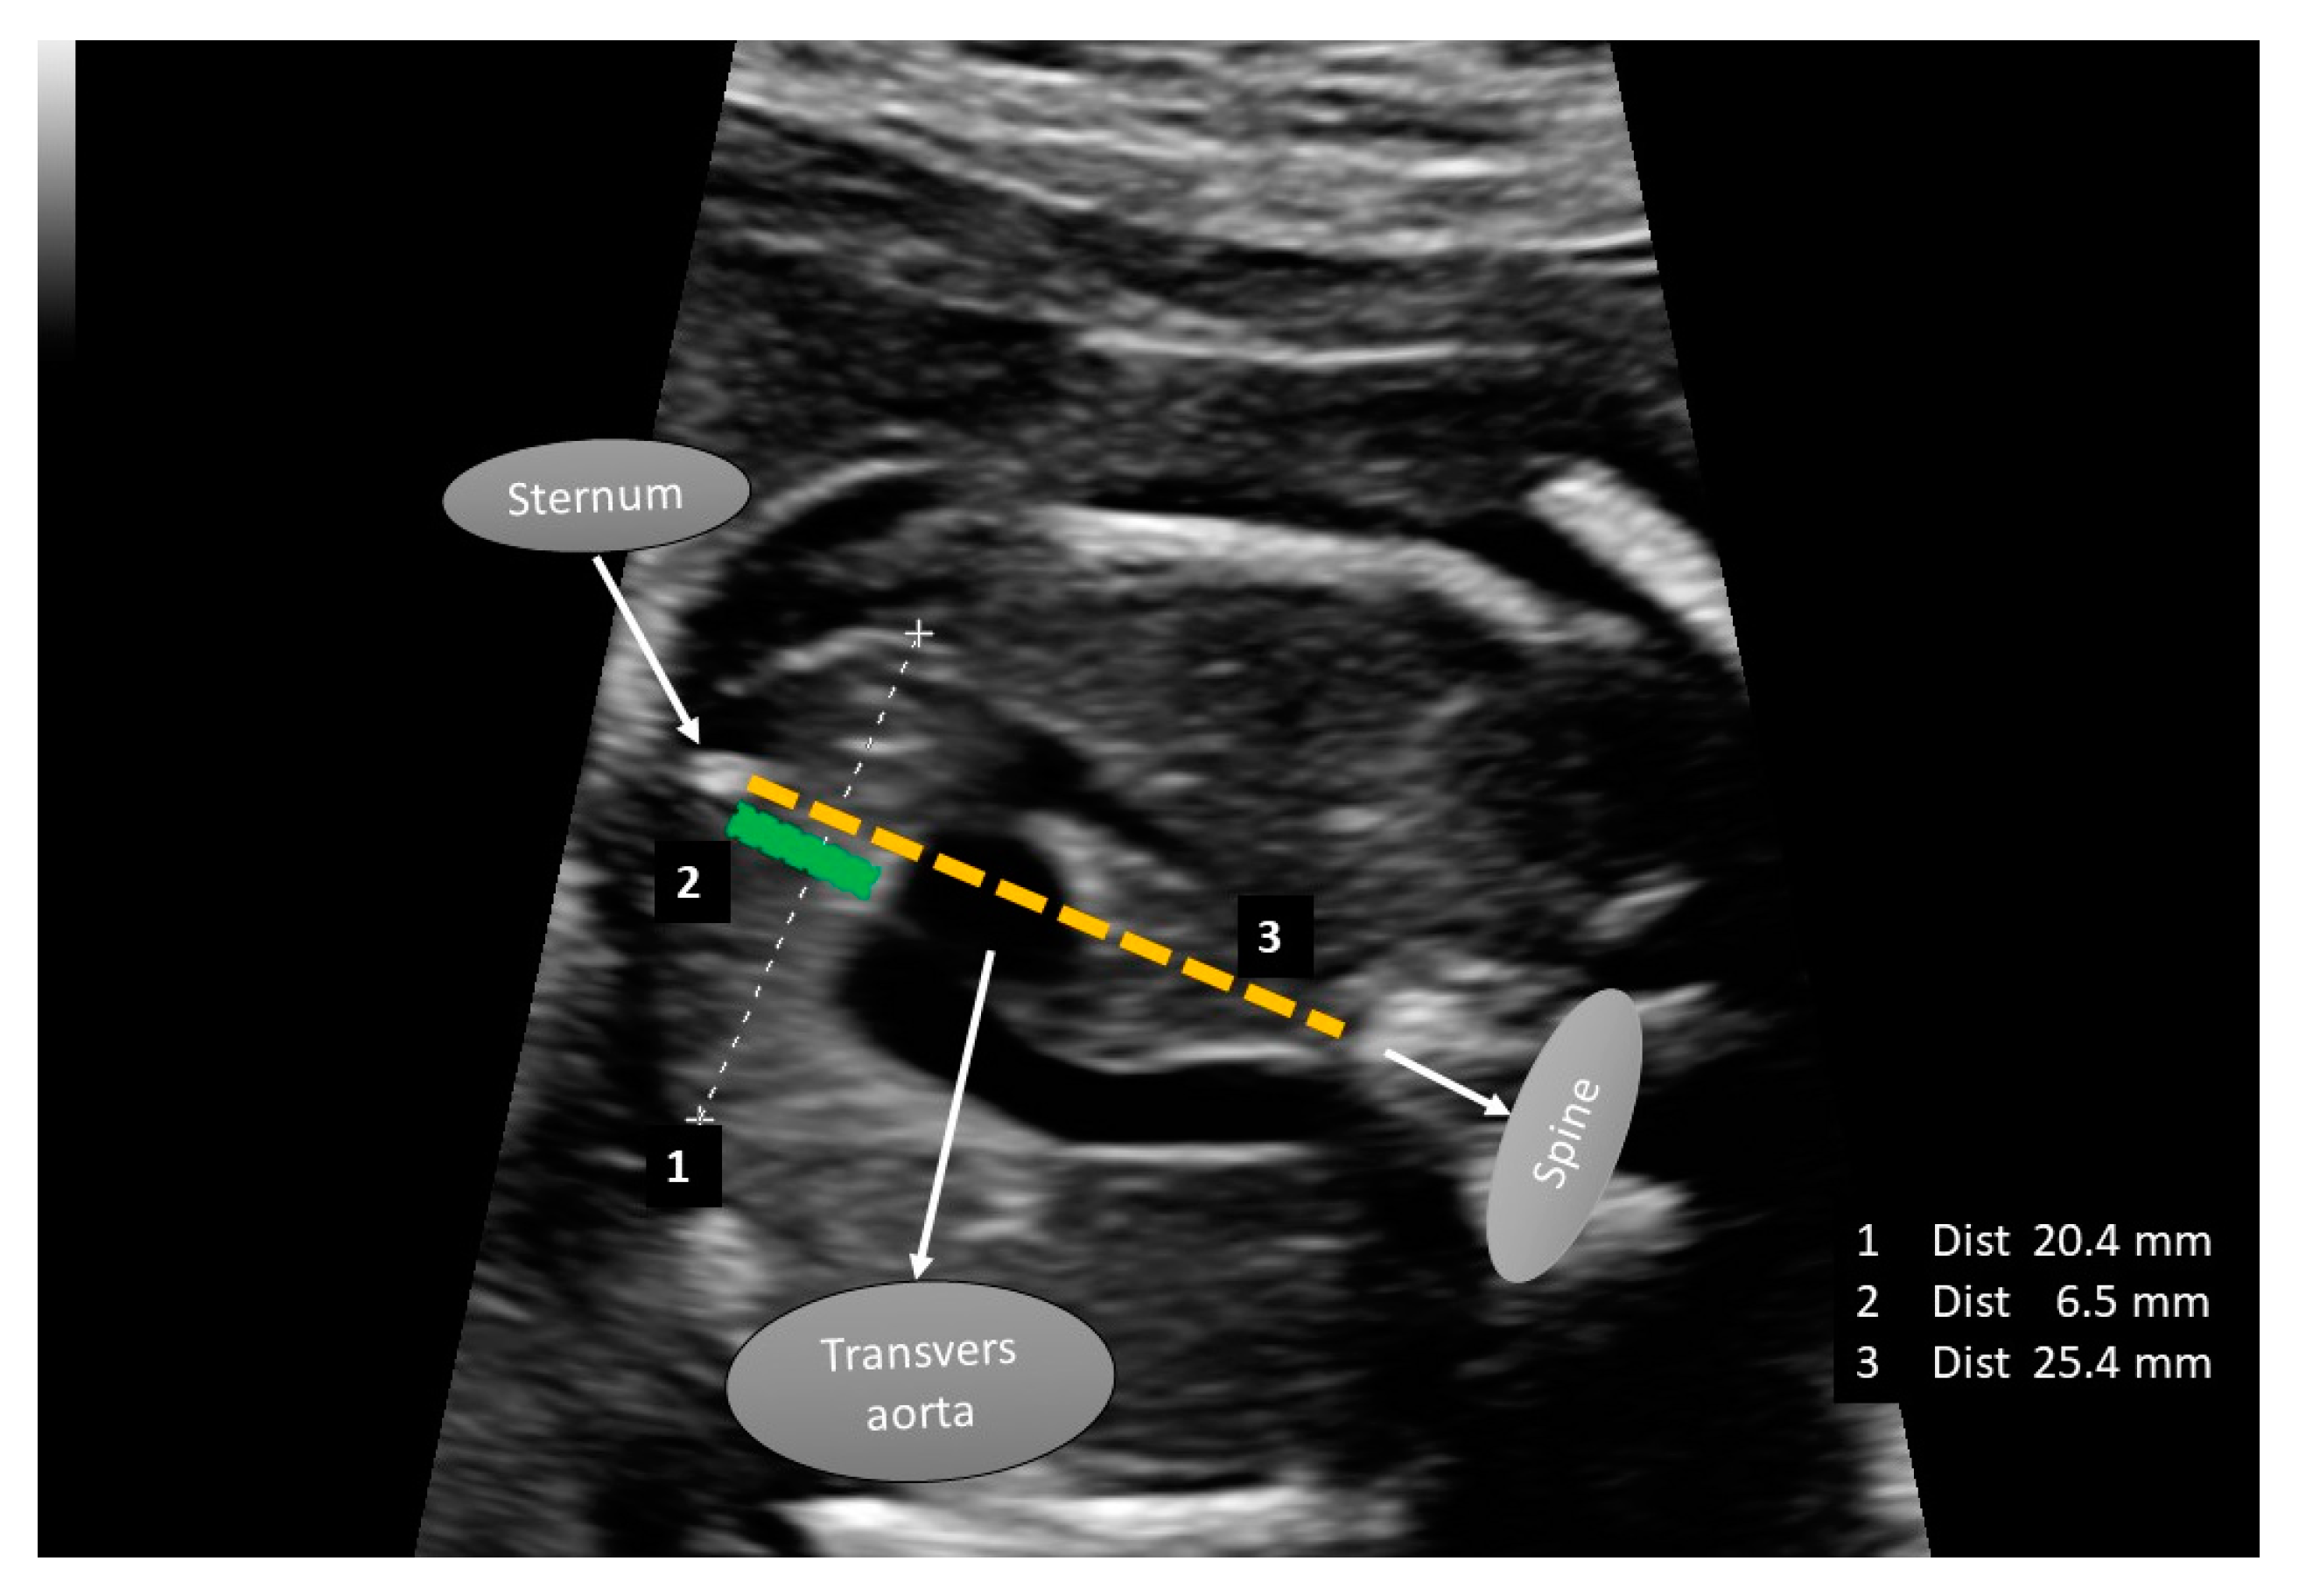

2.2. Fetal Thymus İmage Analysis

| Thymus transverse diameter (mm) | 18 (16–20) | |

| Thymus/thorax ratio | 0.345 (0.290–0.390) | |

| Thymus transverse diameter (mm) | 18 (16–21) | 18 (16–19) | a 0.240 | |

| Thymus/thorax ratio | 0.375 (0.300–0.400) | 0.320 (0.280, 0.350) | a 0.003 * | |